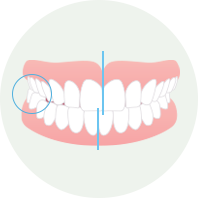

奥歯の交叉咬合

- あごを左右のどちらか、横にずらしてかむ癖がある

- 頬杖や片側だけで食べ物を噛む癖がある

奥歯の交叉咬合の対応

早期(幼児期)にかみ合わせの改善が必要です。成長に伴い、顔貌の対称性に影響し、顎が曲がって成長する可能性があります。